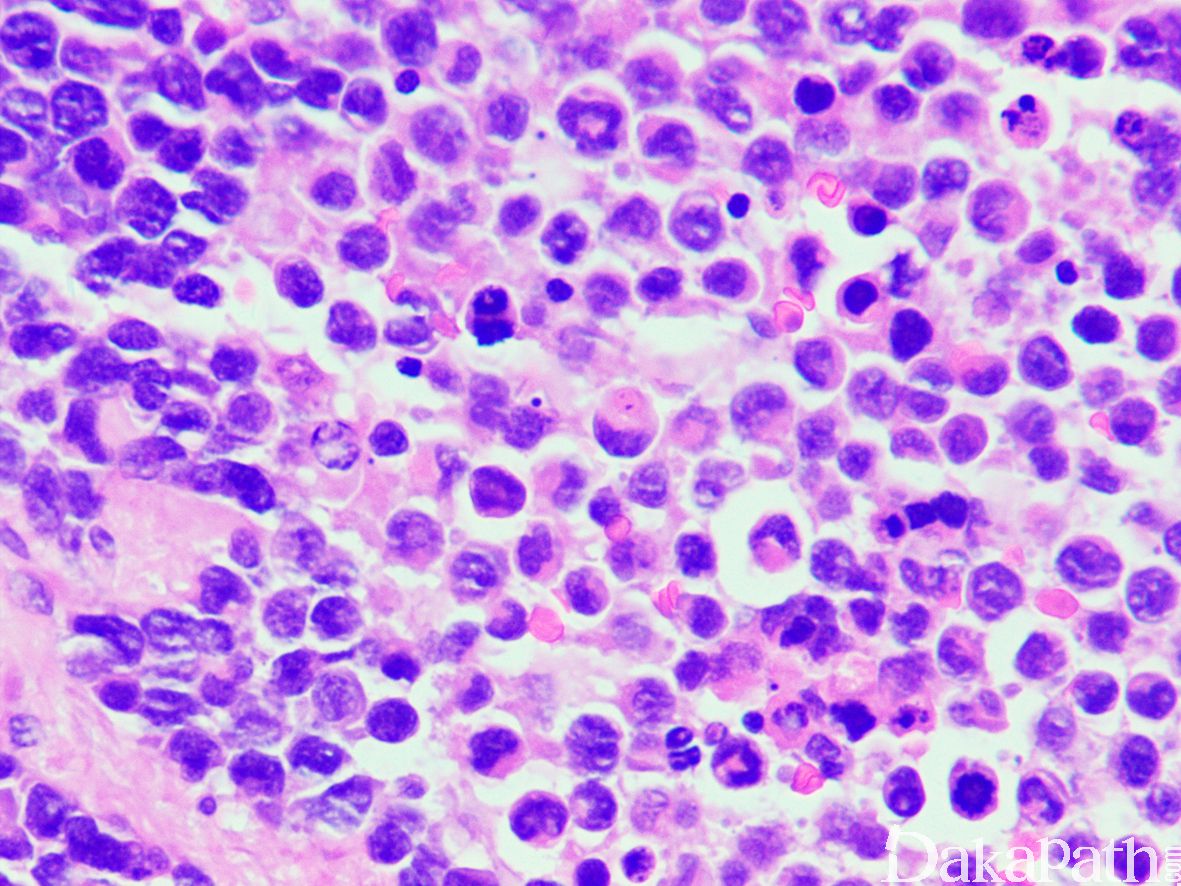

3. 经典型:

4. 瘤细胞排列成片状和巢状而贴附于纤维性间隔上,巢中央瘤细胞黏附性差,相互解离,形成特征性的假腺泡状或微囊状结构;

5. 肿瘤由未分化的原始间叶性细胞及少量早期分化的幼稚横纹肌母细胞组成;

6. 原始间叶性细胞呈圆形、卵圆形或小多边形,胞质少,核深染,核分裂像易见;

7. 腺泡中央的横纹肌母细胞多呈圆形或卵圆形,有时可见到胞质内横纹;

8. 部分病例可见散在的胞质淡染或弱嗜酸性,核位于胞质周边的多核巨细胞;